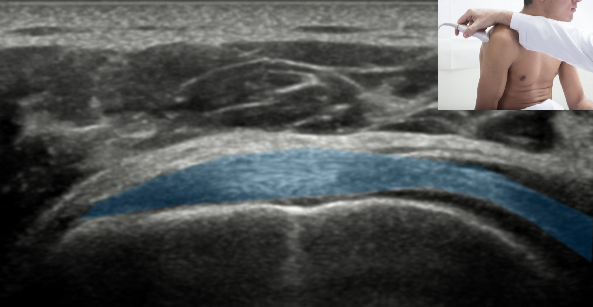

QUAL A ESTRUTURA ASSINALADA NA FIGURA?

TENDÃO DO SUBESCAPULAR (CORTE LONGITUDINAL)